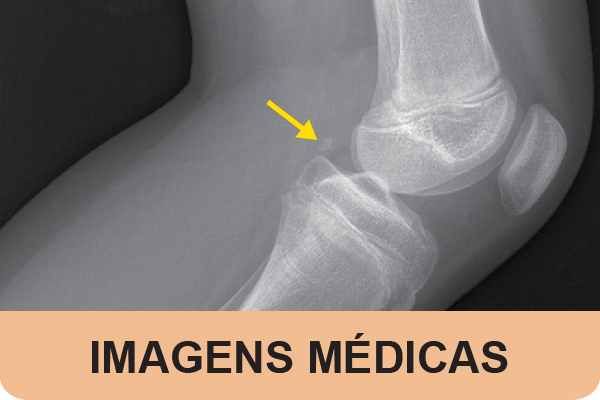

A 12-year-old female patient, followed in Pediatric Rheumatology for oral aphthosis, reported mild-to-moderate lateral right knee mechanical pain for several months, i...